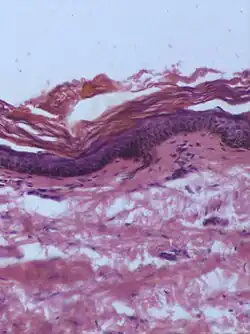

Junctional nevus | Along the junction of the epidermis and the underlying dermis.[15] | May be colored and slightly raised.[16] | ![]() |

ICD10: D22 ICDO: M8740/0 |